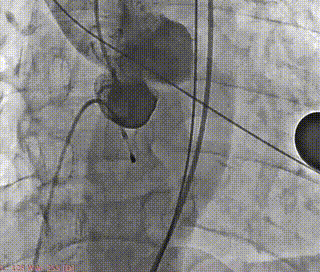

术前造影(左右窦重合体位)

最终造影评估

本次手术植入瓣膜定位准确,操作简便,症状即刻改善。术后超声显示瓣口未见明显反流,微量瓣周漏,主动脉瓣前向血流加速Vmax=1.9m/s,有效开口面积2.9cm²,PGmean=8mmHg。患者生命体征稳定,手术室当场清醒,手术圆满成功。术后复查超声恢复良好,3天后出院。